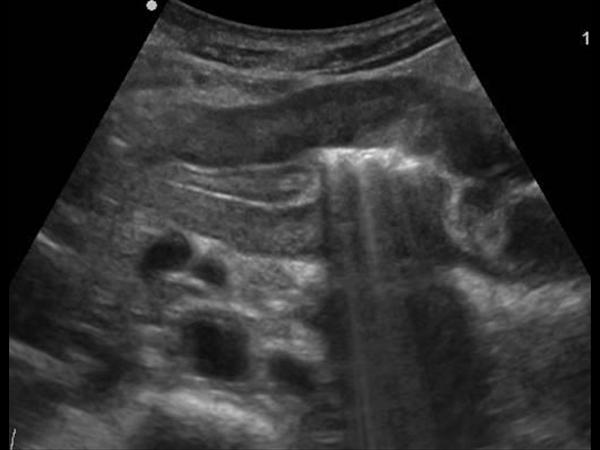

U dạ dày

» Thông tin: Nam giới – 41 tuổi.

» Lâm sàng: Đau thượng vị / Sút cân.